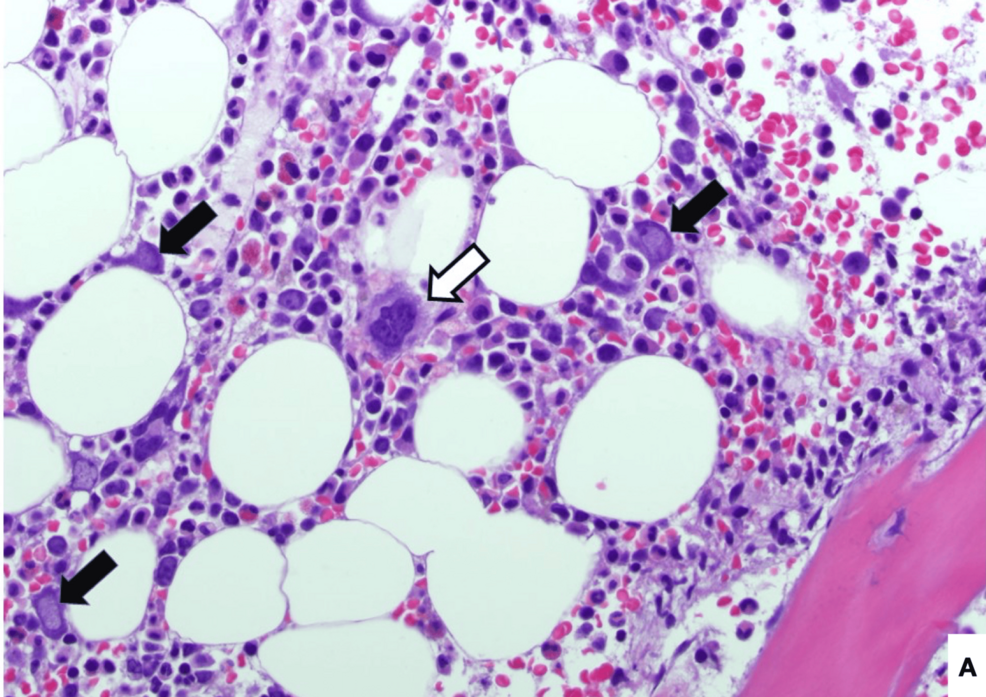

Parvovirus B19 is a common human virus known for causing fifth disease, a mild rash illness, in children. However, in individuals with compromised immune systems, such as those with HIV, parvovirus B19 can lead to more severe and chronic complications, most notably pure red cell aplasia – a condition where the bone marrow stops producing red blood cells. This can result in profound and persistent anemia.

The reason for this heightened susceptibility lies in the virus’s preference for actively dividing cells. Red blood cell precursors, the cells that mature into red blood cells, are rapidly dividing, making them a prime target for parvovirus B19. In a healthy immune system, the virus is typically cleared, and red blood cell production resumes. However, in individuals with HIV, the immune system may be unable to effectively control the infection, leading to its persistence and ongoing suppression of red blood cell production.